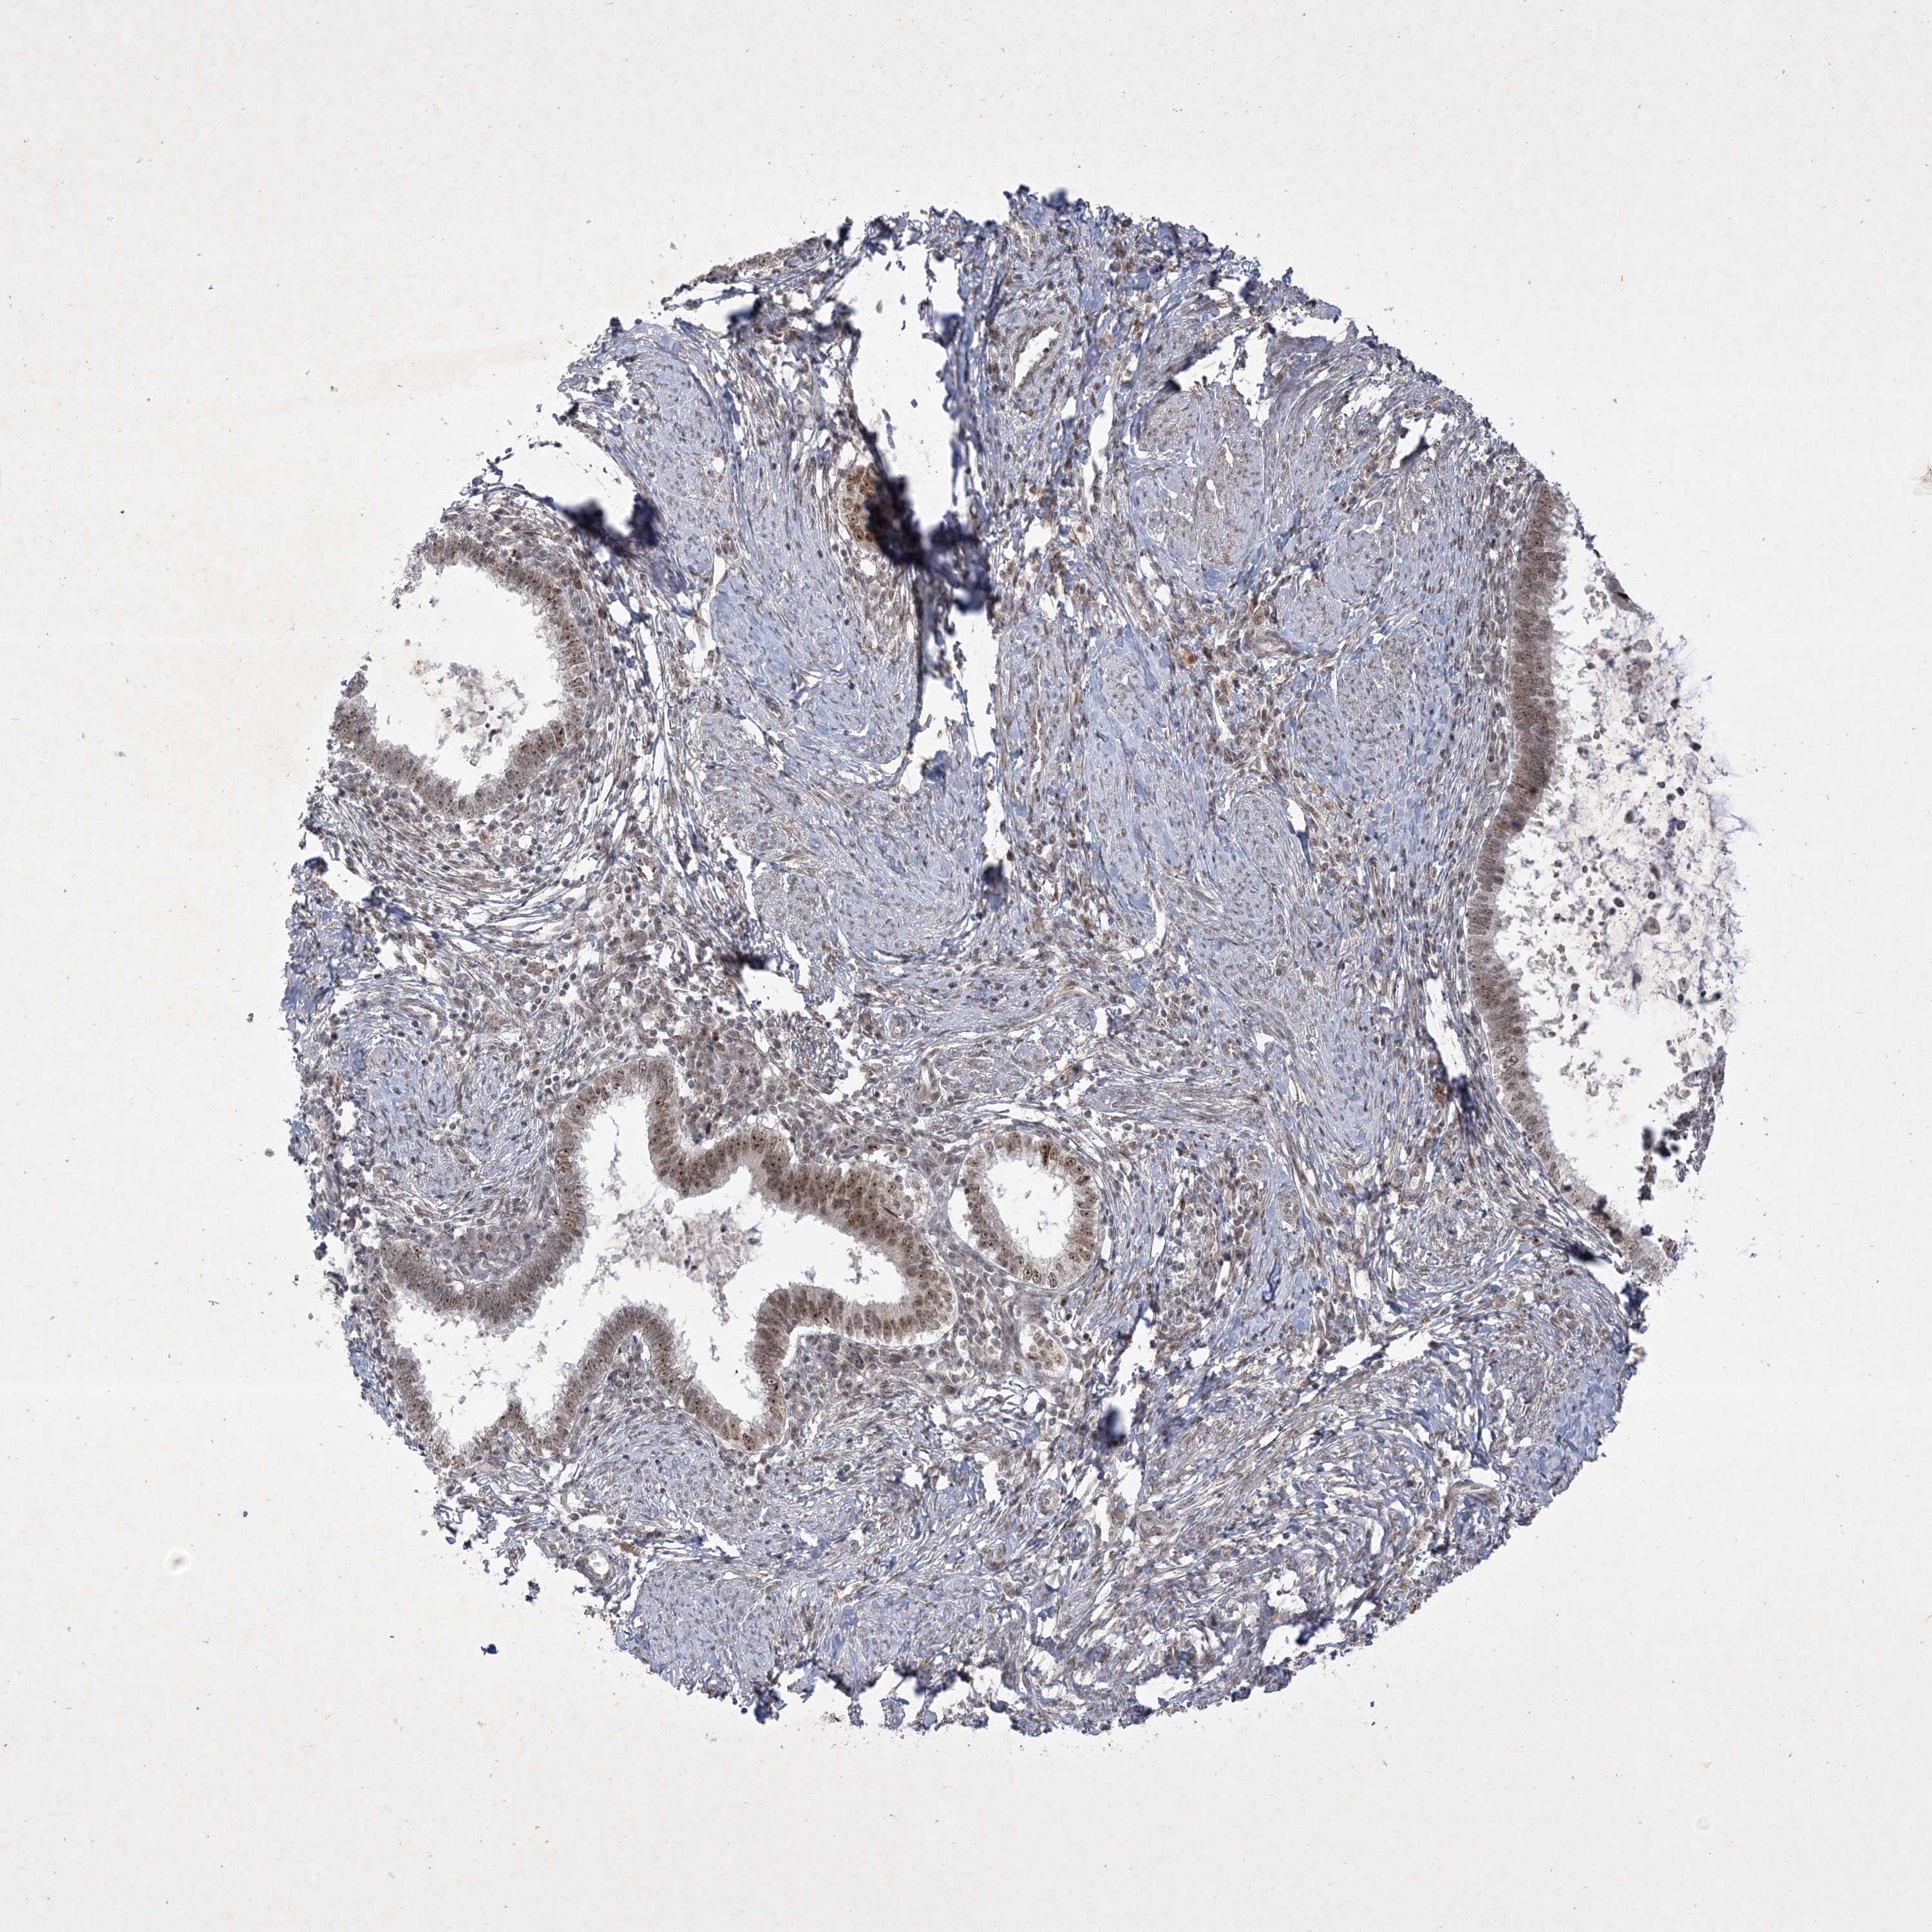

CERVICAL CANCER - Protein expressioni

A mouse-over function shows sample information and annotation data. Click on an image to view it in a full screen mode. Samples can be filtered based on level of antibody staining by selecting one or several of the following categories: high, medium, low and not detected. The assay and annotation is described here.

Note that samples used for immunohistochemistry by the Human Protein Atlas do not correspond to samples in the TCGA dataset.

Antibody stainingi

Antibody staining in the annotated cell types in the current human tissue is reported as not detected, low, medium, or high, based on conventional immunohistochemistry profiling in selected tissues. This score is based on the combination of the staining intensity and fraction of stained cells.

Each image is clickable and will lead to virtual microscopy that enables deeper exploration of all samples and also displays staining intensity scores, fraction scores and subcellular localization as well as patient and tissue information for each sample.

Antibody HPA036295

Antibody HPA036296

Staining

High

Medium

Low

Not detected

Intensity

Strong

Moderate

Weak

Negative

Quantity

>75%

75%-25%

<25%

None

Location

Nuclear

Cytoplasmic/membranous

Cytoplasmic/membranous,nuclear

Squamous cell carcinoma, NOS

Adenocarcinoma, NOS